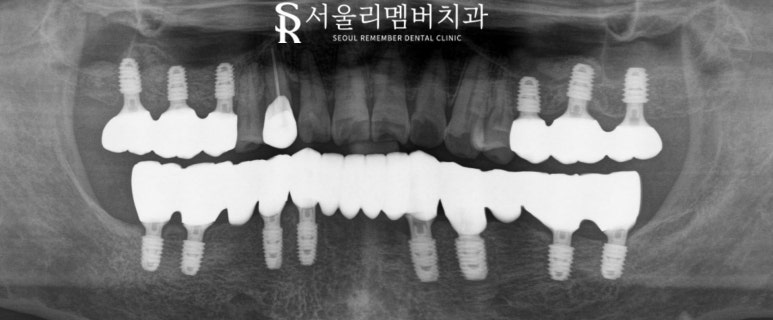

마취 후 편히 치료를

진행하여 추후 보철까지

최종 완성하여 끼워 넣은 사진인데요,

환자의 안모와 수직 고경 또는 교합을

고려해 알맞게 제작되었습니다.

파노라마 사진에서도 가이드대로

정확한 위치에 신경도 다친 곳 없이

잘 치료되었네요.

치료기간 : 2024. 01. 08 ~ 2024. 07.29